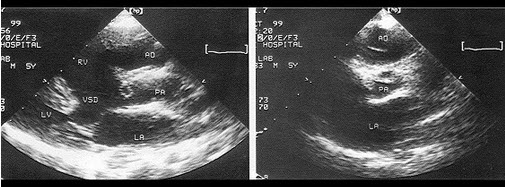

该食管超声心动图显示图像为()

A.房间隔缺损(上腔型)

B.房间隔缺损(下腔型)

C.房间隔缺损(中央型)

D.房间隔缺损(混合型)

E.冠状静脉窦扩张